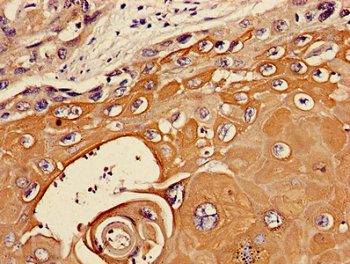

Immunohistochemistry of paraffin-embedded human ovarian cancer using CSB-PA07369A0Rb at dilution of 1:100